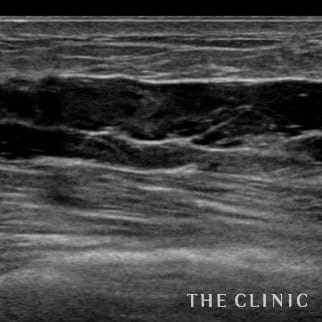

50歳 女性 アクアフィリング(アクアリフト)豊胸のお悩みのアクアフィリング(アクアリフト)豊胸除去

10日前に他院でアクアフィリング豊胸(片胸100ccづつ)を行いましたが、安全性に不安を感じたこと、形や硬さも気に入らないため除去を希望されました。形も悪く、しこりのようになっていました。 エコーをすると乳腺下にアクアフィリングが注入されていましたが、一部は大胸筋内に広がっていました。(写真は乳腺科に見られた大きな塊、黒い部分です。) 処置はエコー下に生理食塩水で溶解して吸引除去でき、無事、形も柔らかさも元に戻りました。治療の概要 アクアフィリング除去+コンデンスリッチ豊胸:乳腺用エコーを用いて、バスト内の状態を確認。その後、生理食塩水でアクアフィリングを溶解する。溶解仕切れない場合には、注射器で吸い出し除去。アクアフィリング の除去後、バストの皮下にコンデンスリッチファット(老化細胞や不純物を取り除いて濃縮させた自己脂肪)を注入。 施術費用 アクアフィリング 除去(会員料金):¥600,000(税込¥660,000)/溶解1部位

コンデンスリッチ豊胸(モニター価格):¥880,000〜(税込¥968,000〜)